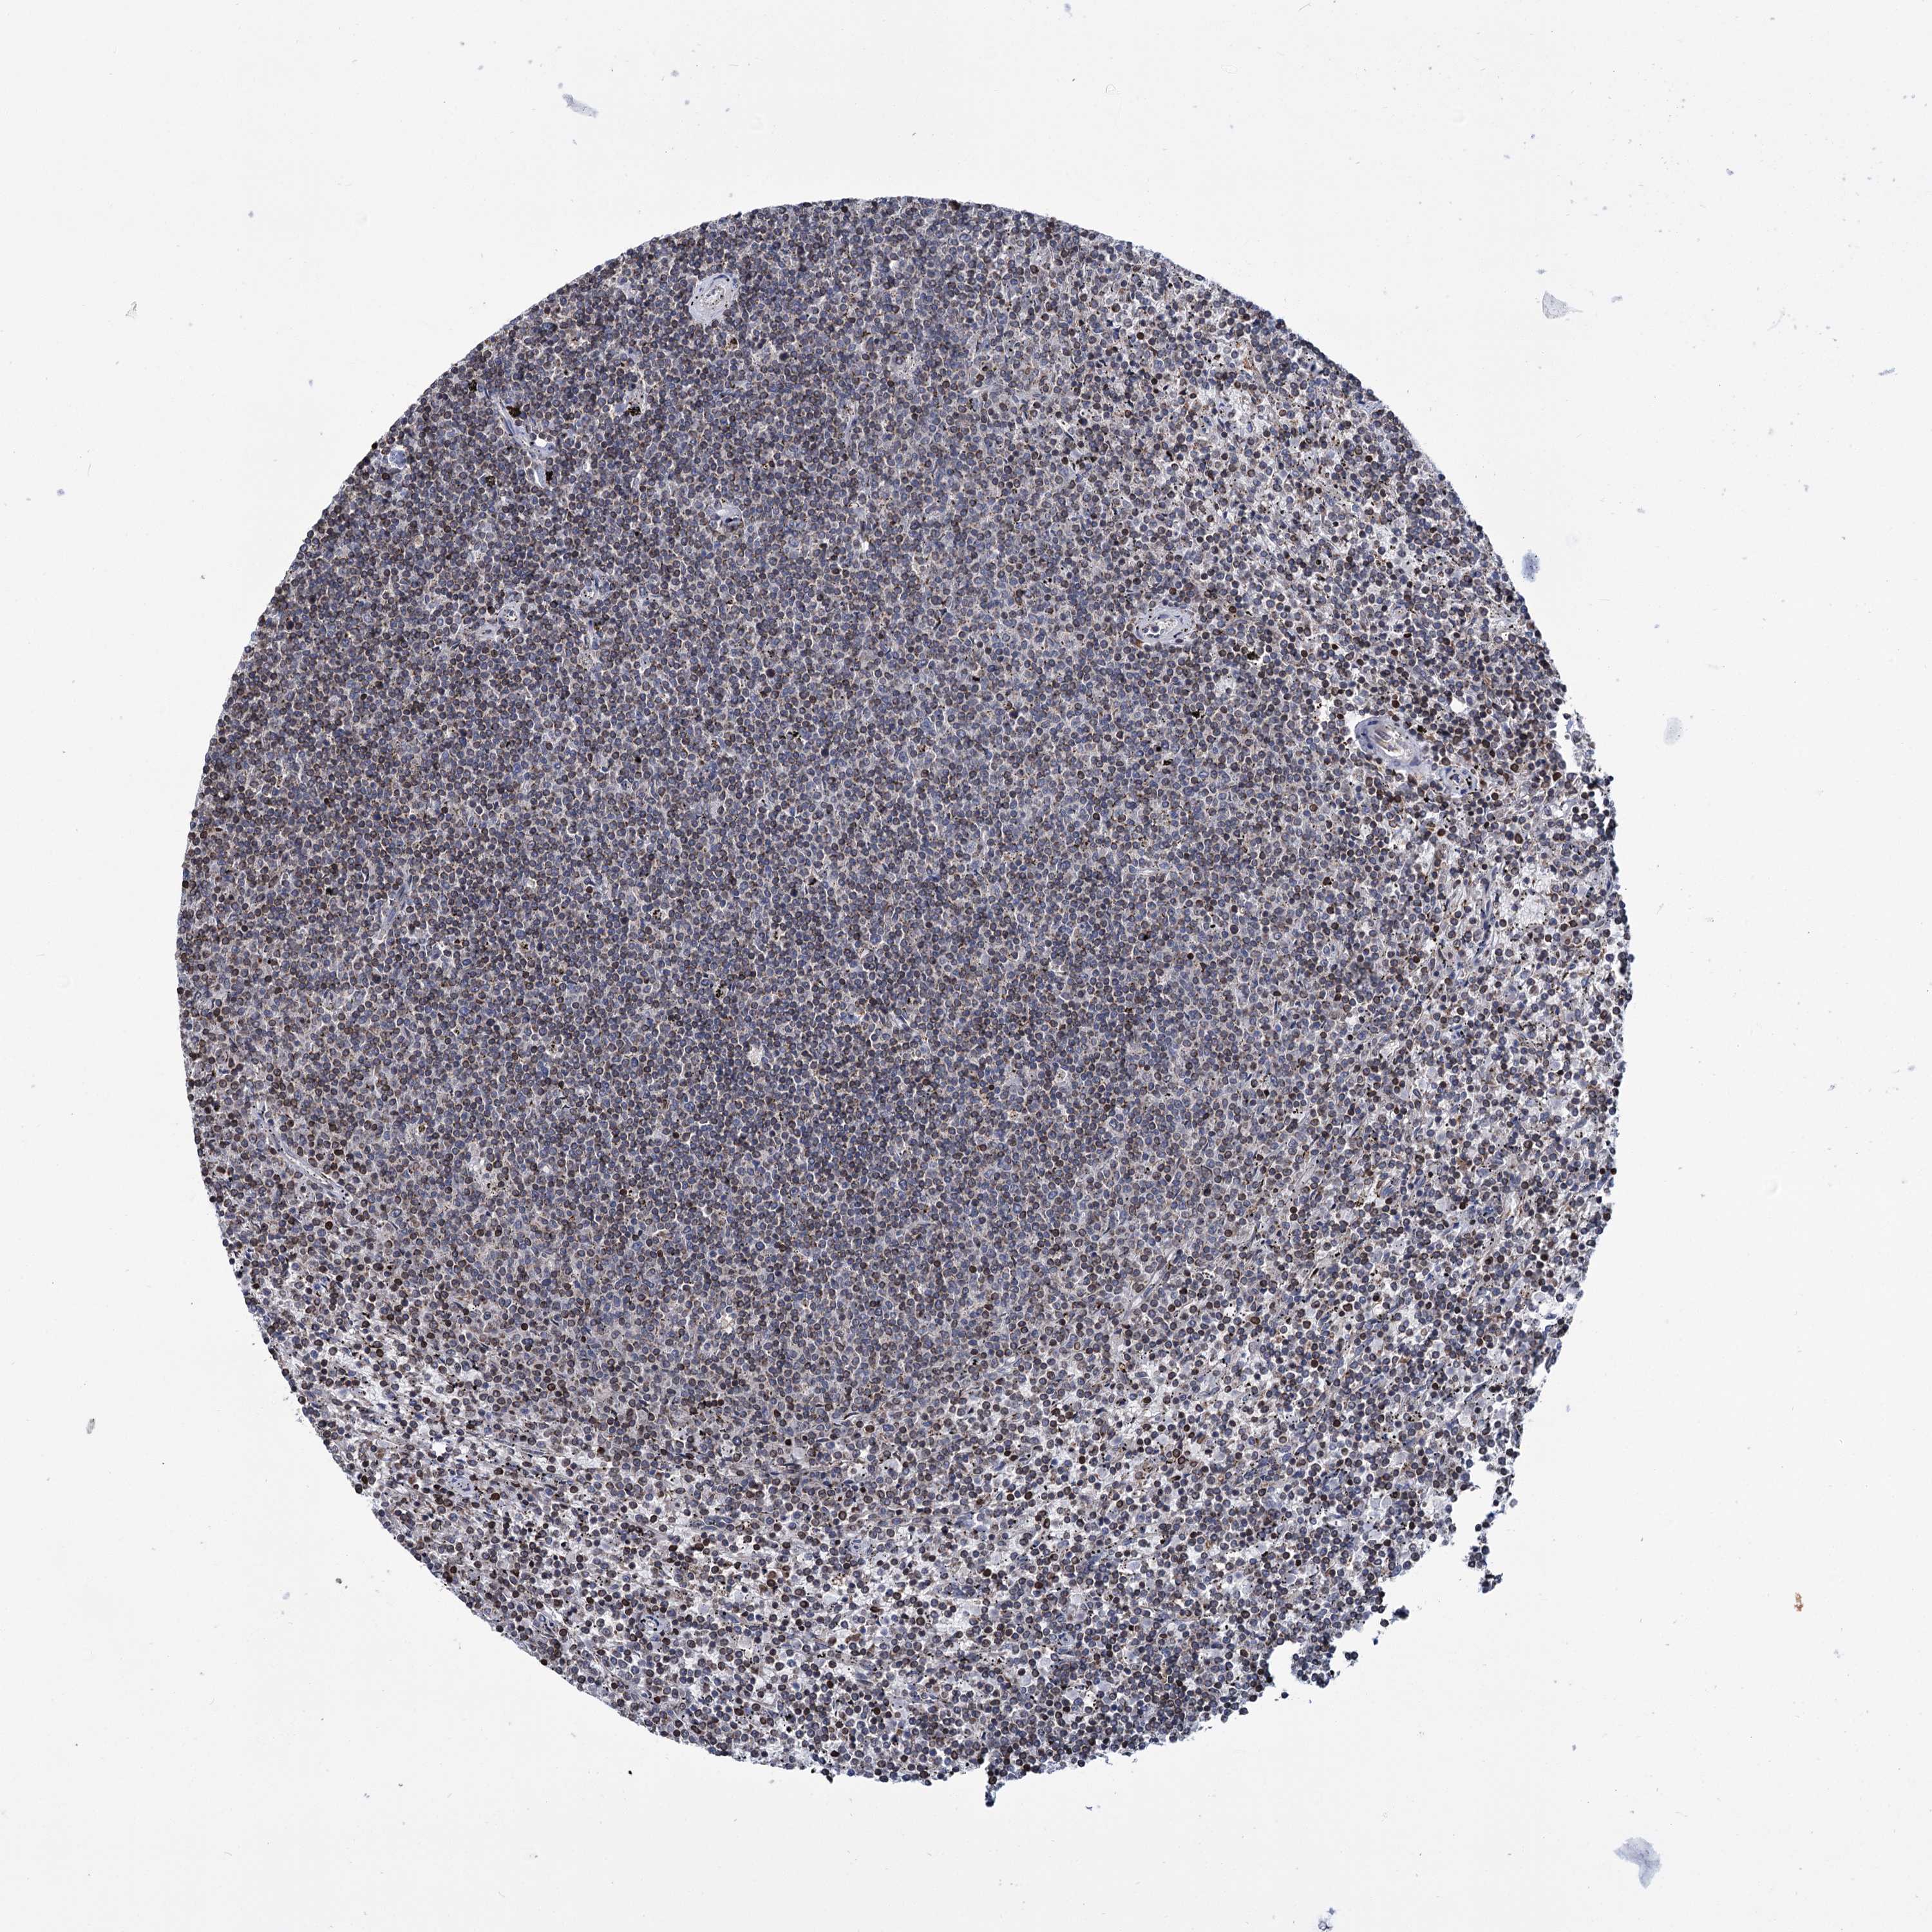

CANCER LYMPHOMA Show tissue menu

LYMPHOMA - Protein expressioni

A mouse-over function shows sample information and annotation data. Click on an image to view it in a full screen mode. Samples can be filtered based on level of antibody staining by selecting one or several of the following categories: high, medium, low and not detected. The assay and annotation is described here.

Antibody stainingi

Antibody staining in the annotated cell types in the current human tissue is reported as not detected, low, medium, or high, based on conventional immunohistochemistry profiling in selected tissues. This score is based on the combination of the staining intensity and fraction of stained cells.

Each image is clickable and will lead to virtual microscopy that enables deeper exploration of all samples and also displays staining intensity scores, fraction scores and subcellular localization as well as patient and tissue information for each sample.

Antibody HPA037786

Hodgkin's disease, NOS

Malignant lymphoma, non-Hodgkin's type, High grade

Malignant lymphoma, non-Hodgkin's type, Low grade